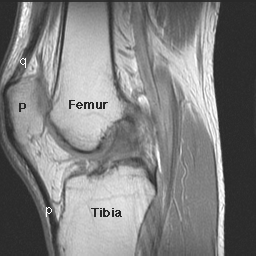

6/6/96 - I laid in the MRI tube motionless for about an hour. They just filmed my knee. I'll pick up the pictures tomorrow to deliver them to the surgeon's office. I'll meet with him on Monday. Surgery is scheduled for next Friday at 12:00.

6/10/96 - We went to see the surgeon this morning. My ACL (one of the knee ligaments) is torn, my lateral (outside) collateral ligaments are torn, and he's not sure about the rest. He will have to study the MRI results for more details.

The damaged nerve is on the lateral side of the knee, where most of the damage was.

Odd that I had a small tear in the anterior (front) part of the medial (inside) meniscus (the knee cushion made up of cartilage). That should heal okay.